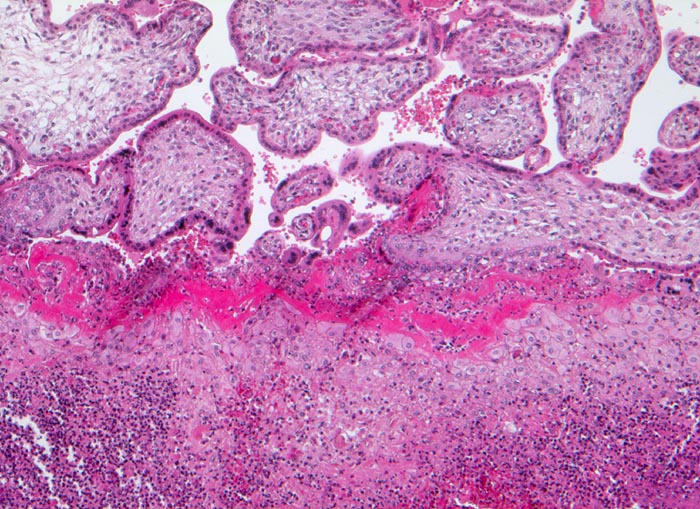

akute Deziduitis basalis (Endometritis)

Einschmelzende Entzündung im Bereich der Dezidua basalis. Daran angrenzend gut erhaltende Plazentarzotten aus Frühschwangerschaft.

hochfieberhafter Infekt der Mutter in der 14. SSW 24 Stunden vor Fehlgeburt. Staphylococcus aureus im Lungengewebe des Feten nachweisbar.

Die infektiöse Entzündung im Bereich der Basalplatte muss abgegrenzt werden von einer blanden Abstossungreaktion nach bereits eingetretenem Fruchttod. Bei akutem Beginn der Entzündung, Erregernachweis im Fetus und gutem Erhaltungszustand der Plazentarzotten kann von einer Infektion ausgegangen werden. Eine basale Plazentitis entsteht seltener hämatogen oder infolge einer fortgeleiteten Endometritis, häufiger bei aszendierter Amnionentzündung mit Übergreifen auf den Plazentarand und die Basis mit konsekutiver Lösungsblutung.